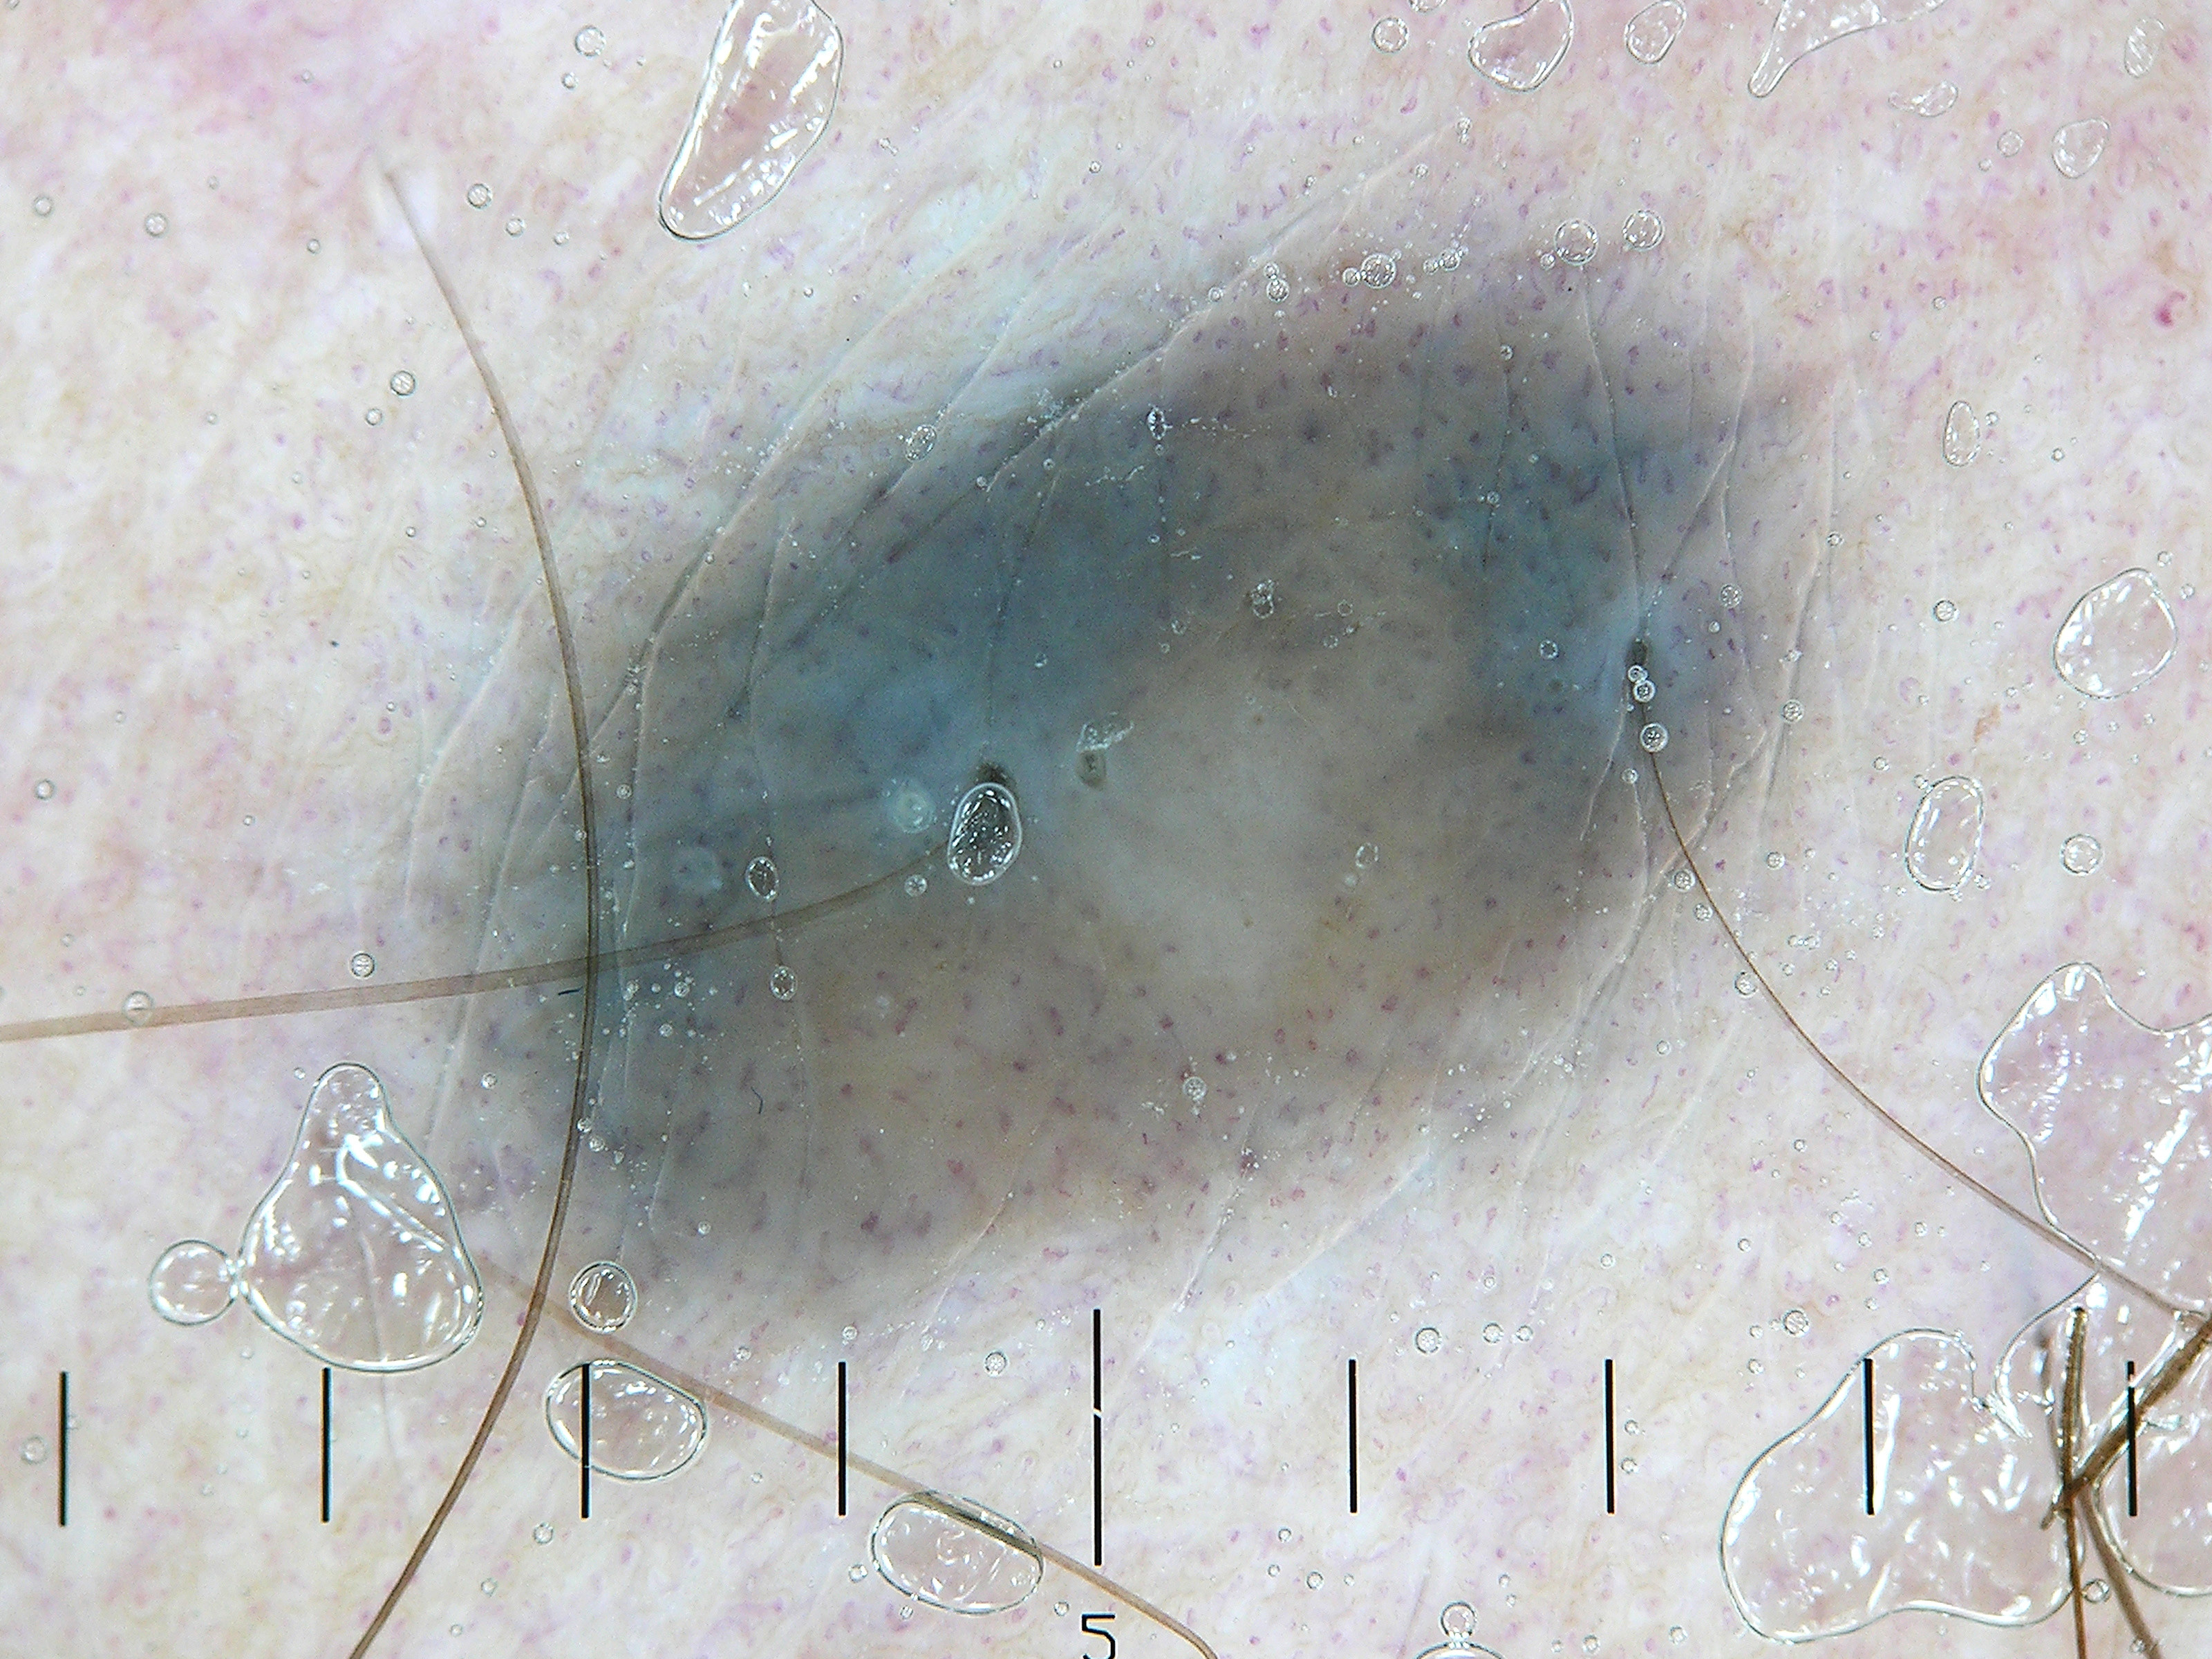

Een

naevus coeruleus (blue nevus)

is een scherp begrensde, meestal solitaire, blauwe tot blauwzwarte subepidermale

vaste nodus. Bij

dermatoscopie maar

ook klinisch ziet men een duidelijke blauwe kleur.

Blue nevus

is de verzamelnaam voor blauw gekleurde, blauw doorschemerende moedervlekken.

Ze kunnen vlak zijn, lichtverheven, of bolrond. De blauwe kleur wordt veroorzaakt

door melanine wat diep in de dermis gelegen is. Dermale melanocytaire naevi

De gewone blue nevus is meestal bolrond (verheven), solitair, geheel of gedeeltelijk

blauw, blauwgrijs of blauwzwart, en tussen de 0.5 en 1 cm groot. Ze kunnen overal

voorkomen, maar de voorkeurslokalisaties (50%) zijn de handruggen en de voetruggen.